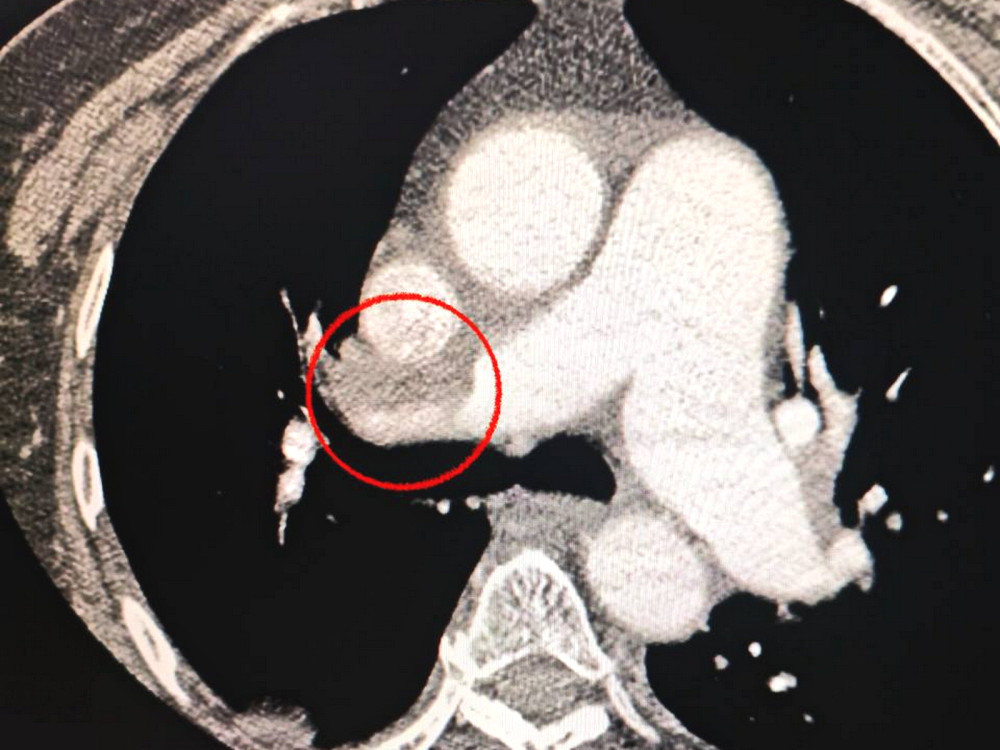

Пациентка, жительница Одессы, была госпитализирована в тяжелом состоянии с острым инсультом. При компьютерной томографии врачи обнаружили закрытие средней мозговой артерии.

Кроме того, медики заметили, что пациентке сложно дышать, что побудило их провести дополнительное исследование легких. Диагноз осложнился тромбоэмболией легочной артерии.